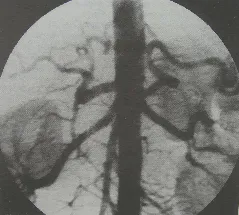

• 3.2 Chụp động mạch đùi:

• Kỹ thuật chụp: Ống thông được đưa vào động mạch đùi chung bên tổn thương để tiến hành chụp mạch. Kỹ thuật chụp mạch được sử dụng là chụp mã hóa xóa nền (DSA), giúp cung cấp hình ảnh với độ phân giải cao và loại bỏ các phần không liên quan đến mạch máu (như xương và phần mềm), giúp bộc lộ tổn thương rõ ràng hơn.